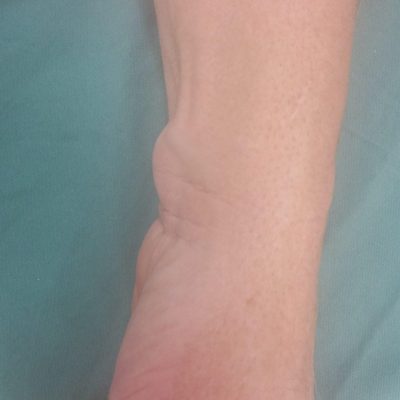

Ganglions are fluid filled cysts that arise from a joint or tendon. A small perforation in a ligament or tendon sheath can create a one way valve where fluid can feed the cyst but not let fluid back out. This can cause a local swelling of a few mm or a 1-2 cm or more depending on the location. Ganglions can be painless or can cause pain and discomfort from pressure and irritation of the surrounding tissues. Ganglions are very common and often found on the back of the wrist, palm of the hand or near the nail, at the DIPJ, but can arise in other parts of the hand and wrist. When they are not causing problems they can be left untreated without risk of long term damage or deterioration and can fluctuate in size or resolve spontaneously.